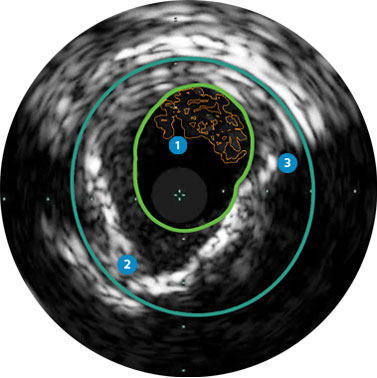

Behandlungsplan Beispiel 2

Lumen mit frischem Thrombus

Mikrokalzifizierung

Kalzifizierte Plaque mit Schallschatten

Gefäßgröße: 6 mm Durchmesser Plaquemorphologie: gemischte, thrombotische Plaque mit mittlerem Calcium Plaquegeometrie: exzentrische Läsion Position des Führungsdrahtes: wahres Lumen

Quick-Cross-Katheter: souverän komplexe Morphologien durchqueren Turbo-Power-Laser-Atherektomie: vorwärts gerichtetes, direktionales Abtragen zur Beseitigung von Thromben; Rotation für verbessertes Abtragen in kalzifizierten Läsionen AngioSculpt Scoring-Ballonkatheter: sicheres Aufweiten von Reststenosen4 Stellarex DCB: entwickelt für hohe Leistungsfähigkeit bei Kalfizifierungen